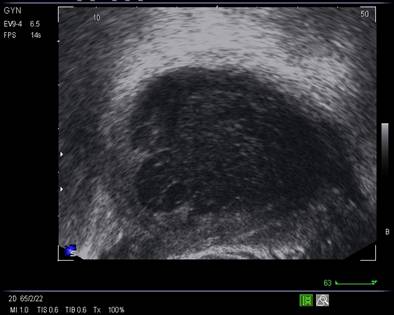

Ovarele. Sectiunea longitudinala directa, spre peretele lateral pelvin, la ecografia transvaginala, pune in evidenta ovarele cu forma elipsoidala. Acestea au structura ecografica relativ slab ecogena, in apropierea si sub vasele iliace.[5]

La pacientele care nu consuma contraceptive hormonale orale se pot identifica usor foliculii selectati preovulator sau corpul galben.

In postmenopauza, disparitia ecostructurii specifice cu foliculi anecogeni si atrofia ovarelor duce la identificarea ovarelor in proportie mult mai mica (de la 96% in premenopauza , scade identificarea ovarelor la 64%, prin ecografie transvaginala [6]).

Marimea ovarelor: inainte de menopauza aproximativ 3,5 x 2,5 x 1,5 cm si aproximativ 2,0 x 1,5 x 1 cm dupa menopauza. Nu se poate aprecia volumul ovarian decat masurand cele trei diametre in planuri sagitale, oblice si coronale ale pelvisului.[1,2,9]